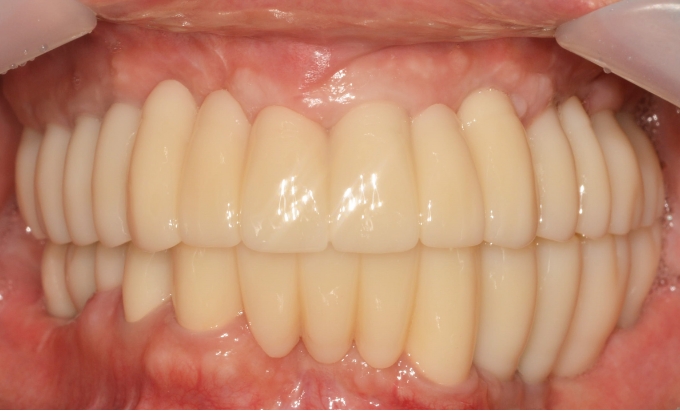

02

2019. 01. 20 ~ 2021. 01. 20

어려운 증례는 비교적 확실한 방법으로 보다 안전하게 식립합니다.

After